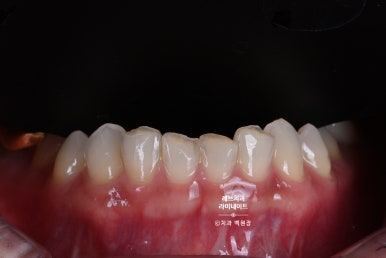

사실 아래 앞니가 거의 보이지 않는 스타일이신데요,

이렇게 위 앞니가 아래 앞니를 덮는듯한 모양을 갖고 계신 분들을 '과개교합'이라고 부릅니다.

레브네이트 치료를 받기로 결정하신 이유는 바로 아래 앞니의 색상 때문이었습니다.

윗니와 아랫니의 색상차이를 확연히 구별하실 수 있겠죠?

위 치아는 라미네이트 치료가 되어 있으시지만, 아래 치아는 자연치 그대로입니다.

사실 안보이는데 굳이 치료를 해야하나?? 라고 생각하시는 분들이 많으실 수 있겠으나...

말씀하시거나 웃을 때 아래 앞니가 누렇게 보이는게 당연지사.

더더구나 치아의 파절과 교모는 갖고계신 치아를 더 못생기게 보이게 하고 있죠.

아울러 치아가 모여있어 (치아의 총생이라고 합니다.) 배열도 예쁘지 않은 상태입니다.

게다가 끊어먹는 면인 절단연은 불규칙하게 닳아있었죠.

사실 정적인 자세로 계실 때 웃으면 잘 보이지 않습니다.

그렇지만, 말씀하시거나 웃을 때 보이는게 많이 신경쓰여하셨던 분입니다.

이렇게 보시면, 확실히 윗 치아와 아래 치아의 차이를 느끼실 수 있을거에요.